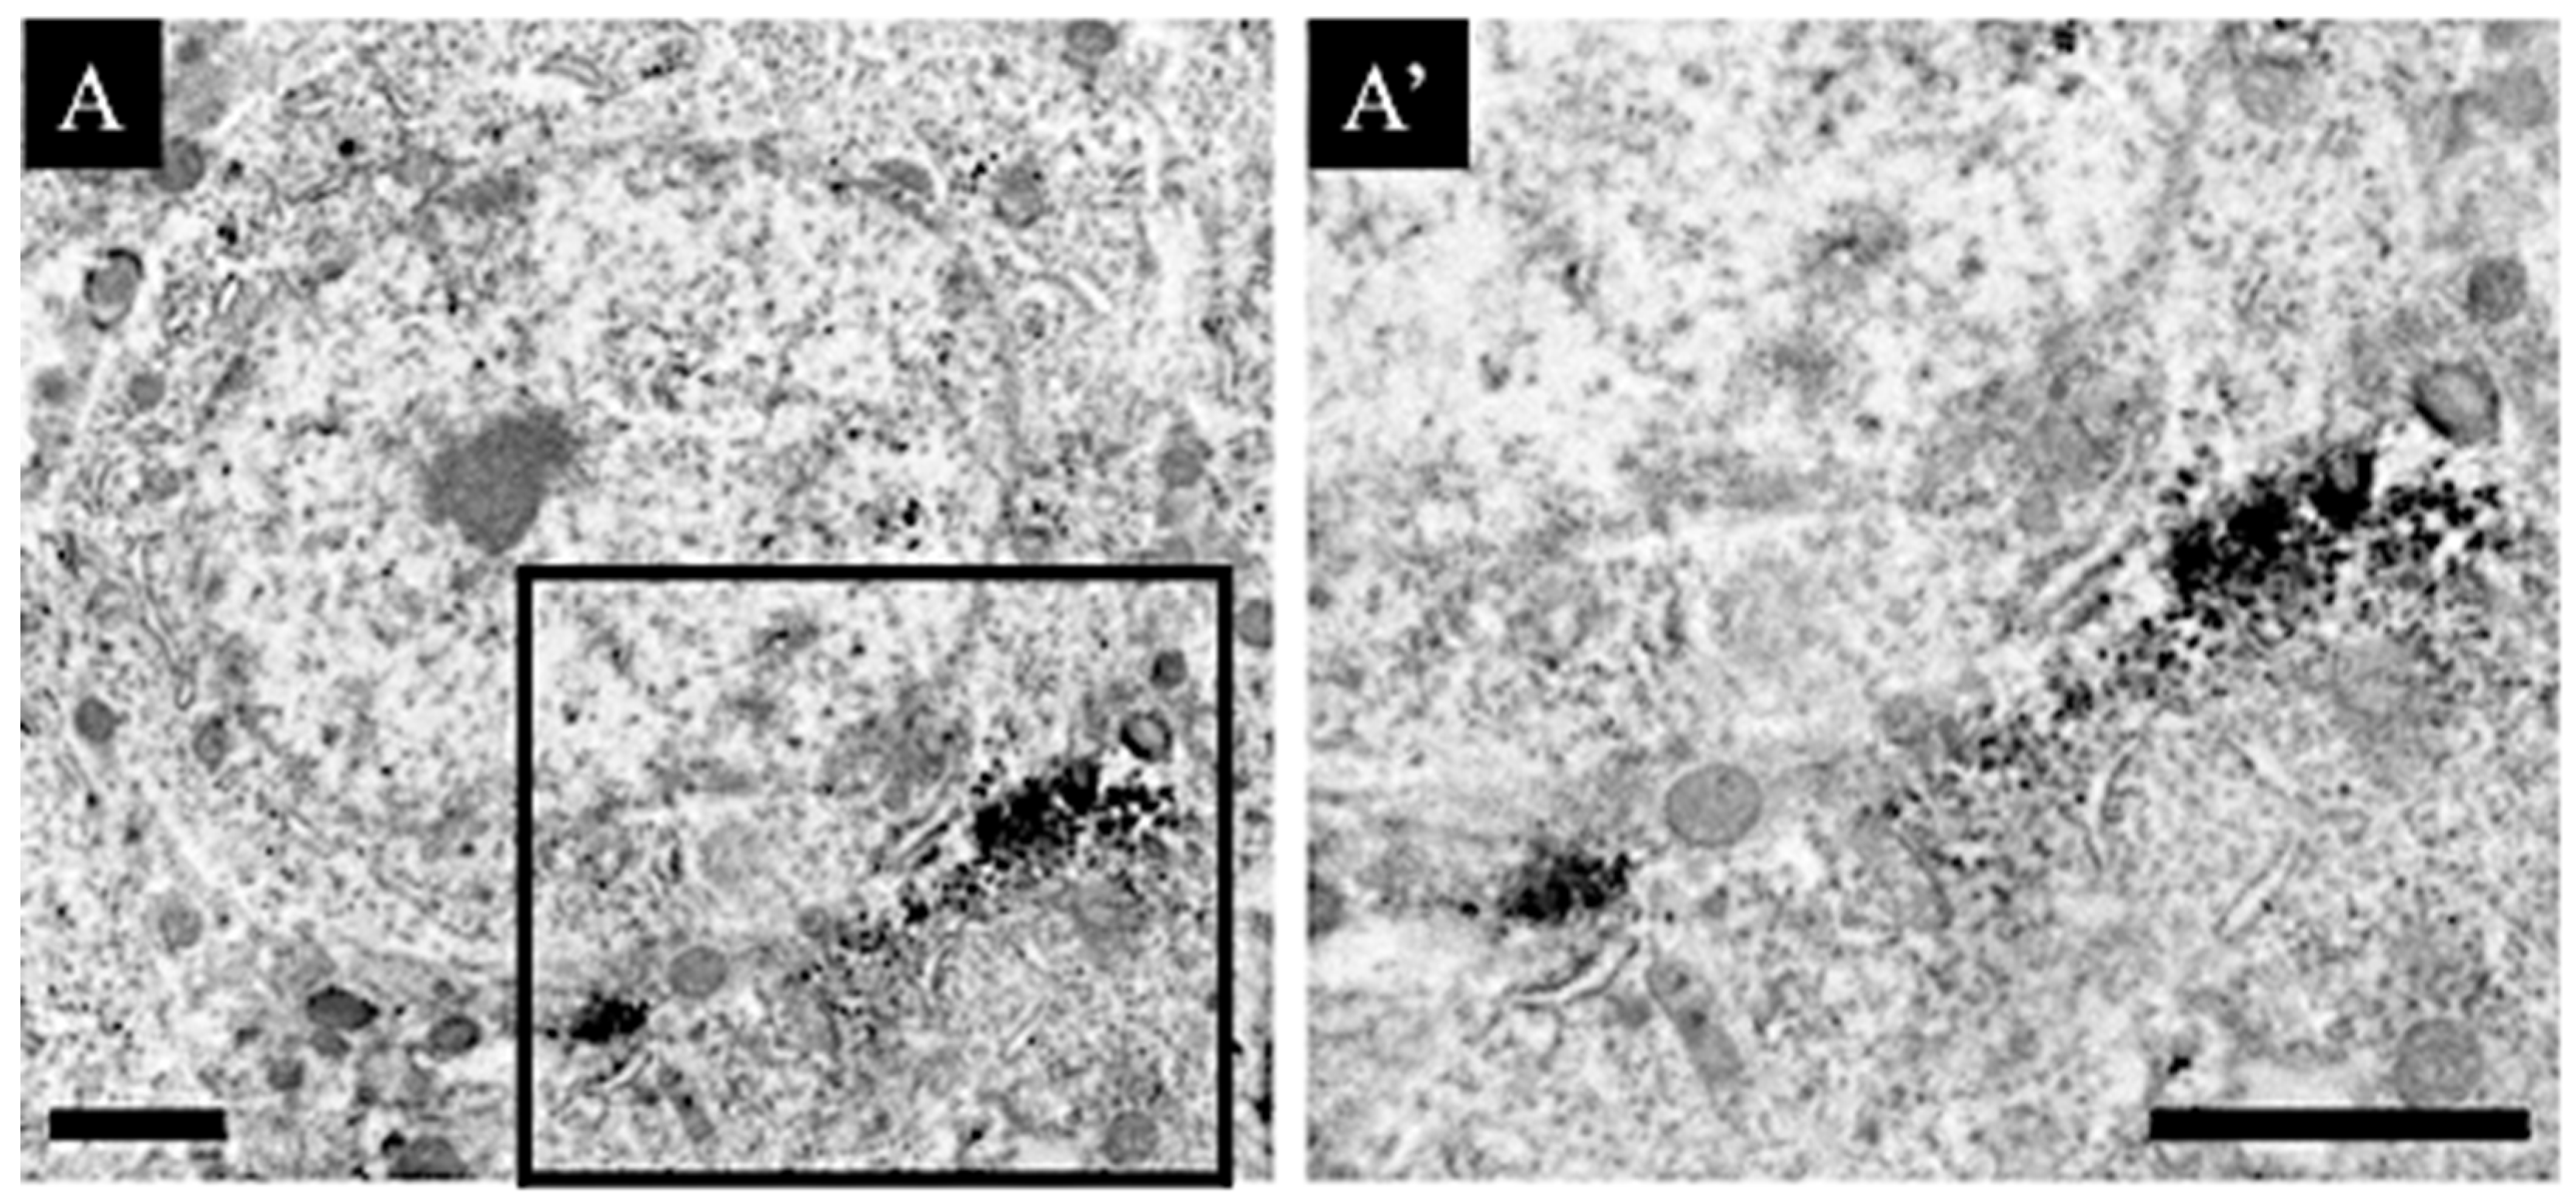

2.5. Immunoelectron Microscopic Analysis

3.3. Distribution Changes in Choline Acetyltransferase (Immunohistochemical and Immuno-Ultrastructural Analysis)

3.4. Distribution Changes in the M1 Muscarinic Acetylcholine Receptors (Immunohistochemical and Immuno-Ultrastructural Analysis)